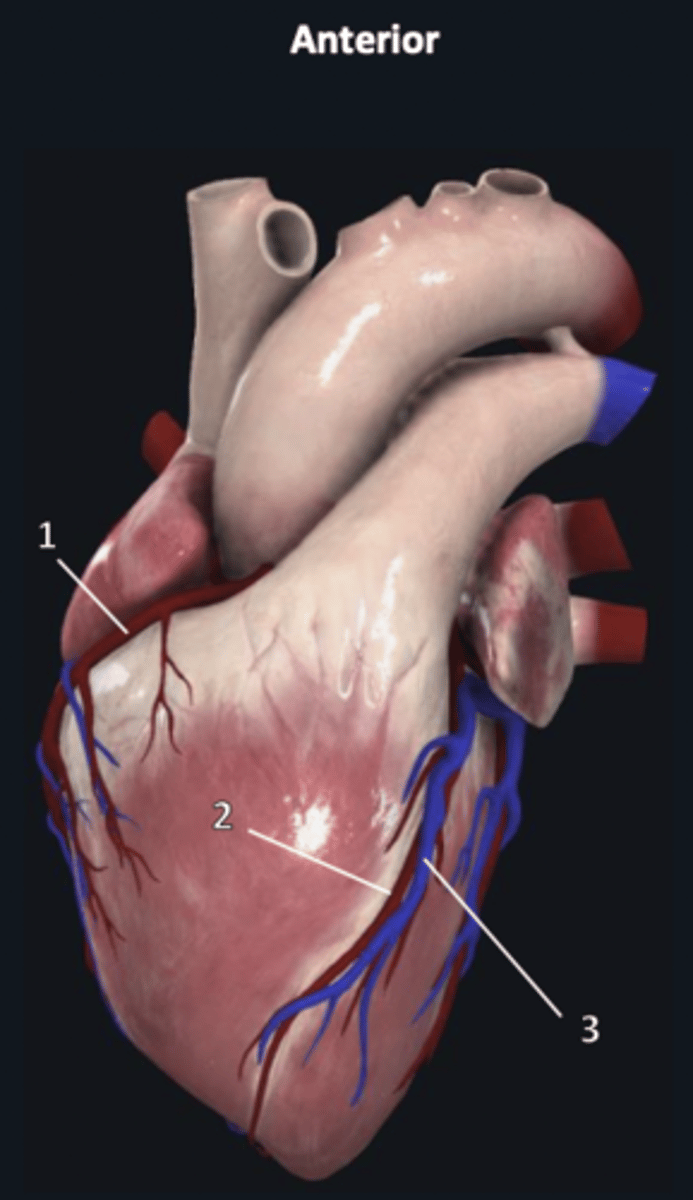

right coronary artery

1

anterior interventricular artery

2 (red)

great cardiac vein

3 (blue)

anterior interventricular artery

2 (red)

great cardiac vein

3 (blue)